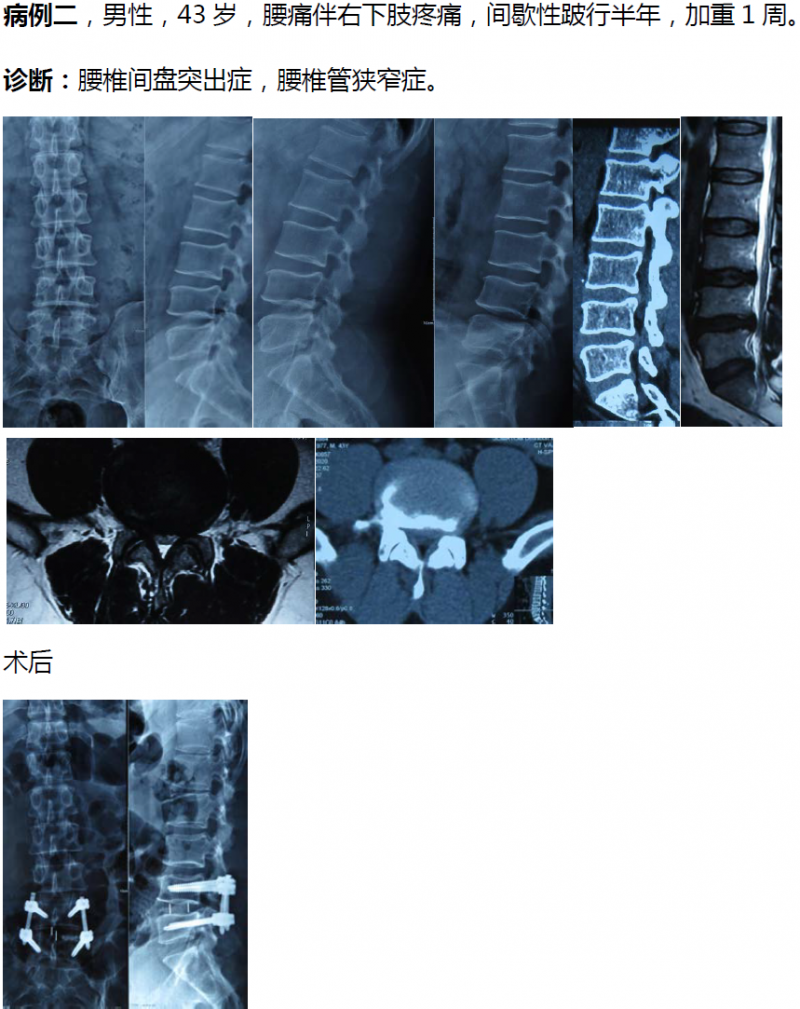

病例分享:(滑动查看)